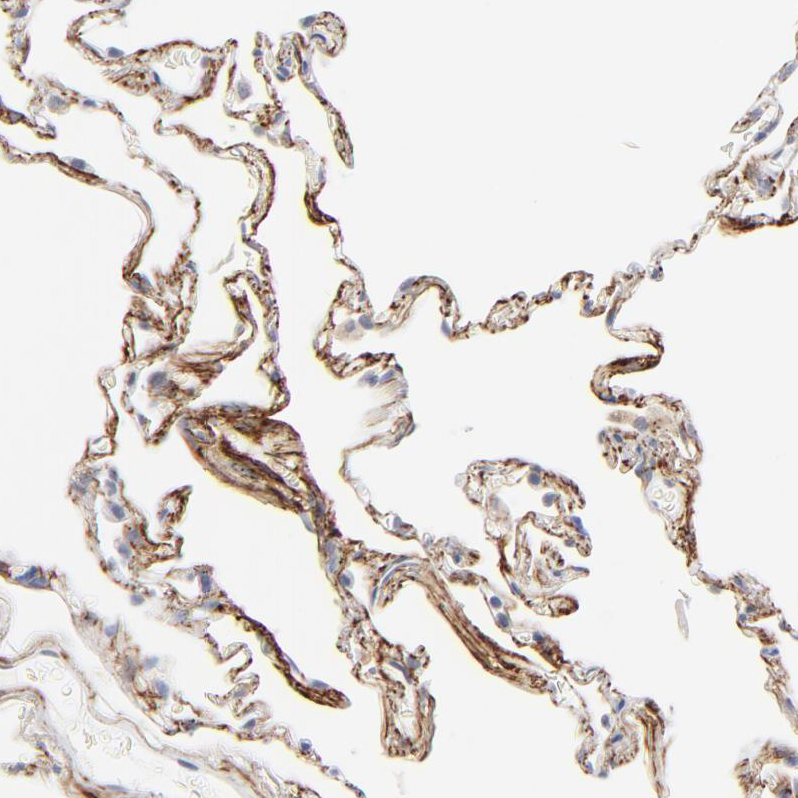

Immunohistochemical staining of human lung shows strong positivity in extracellular space in pneumocytes.